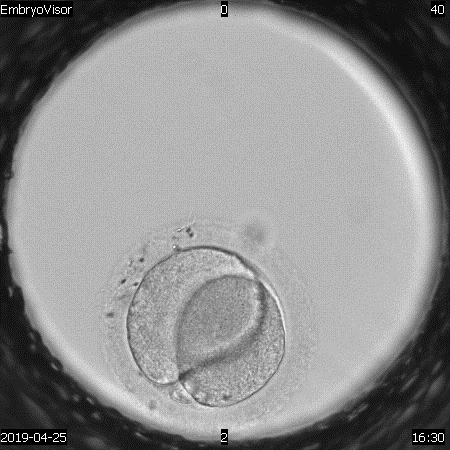

During the analysis of video files, we can state signs of normal -2PN2PB or abnormal fertilization (3PN) (Fig. 1, 2). The second feature is reverse crushing. If it is detected in the development of the embryo, this reduces its chances of implantation in the presence of others in which we have not recorded this feature (Fig. 3). The presented series of images show a series of frames that show the dynamics of the development of this process. In the first case, the embryo, which began division from the three-cell stage, goes through the stage of reverse cleavage into the two-cell stage. The appearance of multinucleation (several nuclei in developing blastomeres) is also a reason to exclude embryos for transfer and cryopreservation if other embryos of comparable quality are available.

Monitoring the process of embryo development makes it possible to fix various stages of morphokinetic transformations, to establish the presence of cytoplasmic and extracytoplasmic structuresmultinucleation, fragmentation, vacuolization, etc., and also to evaluate their contribution to the early development of embryos [15,16]. At present, it is extremely important to identify the predictors of the development of a competent embryo, which determine its implantation potential [17]. Predictors in this case are prognostic parameters, the evaluation of which together serves as a method for differentiation and selection of embryos. For non-invasive monitoring of the preimplantation development of human embryos, a multigas incubator with a reduced oxygen concentration (5%) with a video surveillance system Embryovizor (Westtrade, Russia) was used [18]. This equipment allows, without taking out a dish with developing embryos, to evaluate the first cell divisions, to determine the time intervals of embryo crushing, compaction and formation of blastocysts, and also detects intracellular changes [19].

Transvaginal ovarian puncture was carried out at 36-37 hours after the start of the ovulation trigger. The identification of oocyte-cumulus complexes in the follicular fluid was carried out using a Nikon stereomicroscope (Japan), after which they were removed with a sterile micropipette. The complexes were washed and cleaned from liquid and blood using a HEPES buffer solution (G-mops, Vitrolife, Sweden). After counting the oocytes, they were transferred to special cups with a central well (Nunc) containing G-IVF+ culture medium (Vitrolife, Sweden) for pre-incubation for 2-3 hours (conditions: CO2 -6%, O2 -5%, at a temperature of 37º. After incubation, mechanical and enzymatic removal of cumulus cells (denudation of oocytes) was carried out. In this case, the complexes were placed in a hyaluronidase solution for 30 seconds, followed by washing from enzymes in a buffer solution by a mechanical method. 5-6-day old blastocysts were examined according to a system based on classification (D.K. Gardneretal., 1999) and the RAHR Guidelines "Evaluation of oocytes and embryos" (Russia, 2021) [8,9]. Over 100 cycles were analyzed using TimeLapse technology. The video surveillance system for embryo development included an incubator with an installed video camera Embryovizor (Russia). Embryos were cultured in special WOW dishes (Vitrolife, Sweden) in a universal medium Continius Single Culture (Irvine Scientific, USA) from 1 to 5-6 days of cultivation. There were no specific criteria for selecting patients for culture using this system [10]. The system has direct on-line access. To assess the development of embryos from days 1 to 5-6 of in vitro cultivation, the time of the first cleavages, the time range between the first and second cleavages, as well as the nature of cleavage (morphokinetics), and the time of blastocyst formation were taken into account. All of the above criteria served as predictors of the selection of embryos for transfer [11].